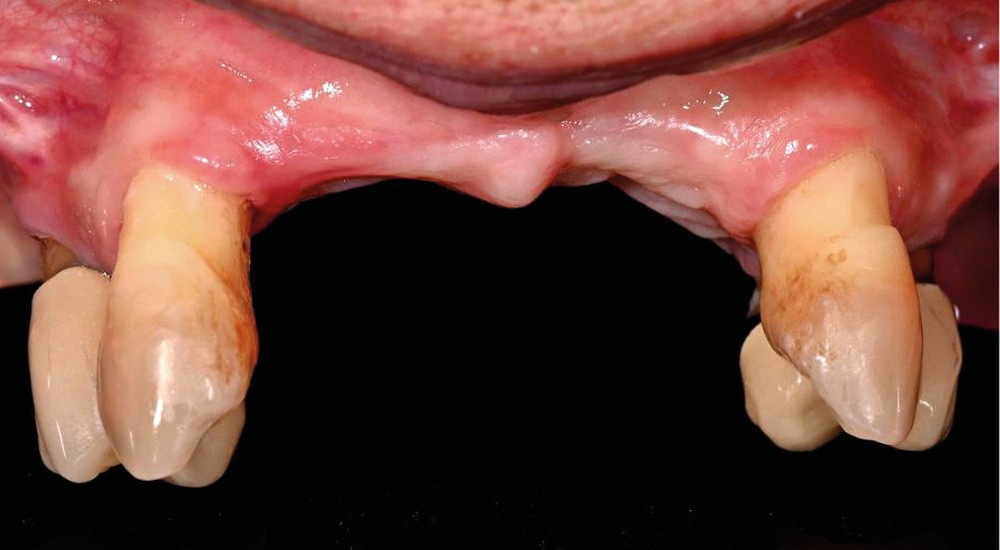

Une patiente de 62 ans, non fumeuse Asa1, porteuse d’une prothèse amovible partielle (PAP) mandibulaire et maxillaire, souhaite bénéficier d’une solution fixée. Il persiste au maxillaire 13, 23, 14 et 24, associées à une forte résorption type FP3 [1, 2] (fig. 1).

Dans un premier temps, un double sinus lift et une nouvelle PAP maxillaire ont été réalisés afin de valider le futur point interincisif et de stabiliser l’occlusion. Les dents restantes ont été conservées afin d’optimiser la stabilité de la PAP pendant la période de cicatrisation et de les utiliser dans un protocole d’extraction-implantation avec mise en charge immédiate en utilisant des guides à étages. Cela permet d’éviter une greffe antérieure 3D complexe associée à un Nasal lift.